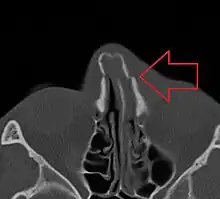

Nasal bone fracture Bilateral nasal fracture as seen on CT scan

Bilateral nasal fracture as seen on CT scan